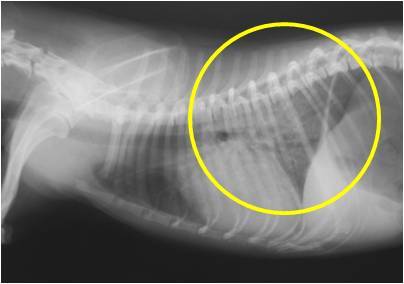

이러한 심청진 으로 심장의 이상을 의심하며, 흉부 방사선을 촬영 하였는데

폐 뒤 쪽으로 심하게 폐 수종이 관찰이 되었습니다.

조금 확대를 하여서 보변 심한 폐수종을 확인 하실 수 있습니다 (노란색 원)

폐란 원래 공기로 차 있기 때문에 방사선 검사상에서 검게 보여야 하는데

폐의 앞쪽( 노란색 원이 없는 곳 )과 뒤쪽( 노란색 원)을 비교해보면

검은 부위와 하얀 부위가 구별되는 것을 보실 수 있을실 겁니다.

이런 검은 부위는 정상적인 기능을 하고 있는 폐이고

하얀 부위는 폐 안에 부종 또는 염증 떄문에 정상적인 기능을 하지 못하고 있는 상태라고 보시면 됩니다.